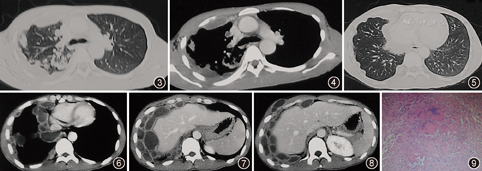

患者男,24岁,无业。3个月前因受凉后出现咳嗽,咳少量白色黏痰,伴发热,最高体温38.5 ℃,热型不详,无畏寒、盗汗、咯血和胸痛,右下胸壁出现一无痛柔软包块,在当地医院使用青霉素等抗感染治疗,1周后体温正常,仍有间断咳嗽,咳少量黄色黏稠痰,胸壁包块逐渐增大。在广州市某肿瘤医院就诊,胸部CT示胸膜多发囊性病变,右胸壁肿物穿刺涂片可见坏死及炎症细胞,未见癌细胞。患者于2007年10月11日在广州医学院第一附属医院呼吸疾病研究所就诊,以胸膜多发囊性病变待查入院。患者既往从事车床加工1年余,吸烟史4年,每日约5支,曾有生食芫荽菜史,无其他病史,发病以来体重减轻约2 kg。体检:体温36.7 ℃,呼吸22次/min,血压108/66 mm Hg(1 mm Hg=0.133 kPa),皮肤黏膜未见异常;双腋下可触及多个淋巴结,直径约为1.5 cm,光滑、无压痛、活动度好;右前下胸壁可见一直径约为3.5 cm的类椭圆形肿块,大小随呼吸运动无明显改变,无压痛,皮下无滑动感;剑突处右侧腹壁可见一直径约为1.5 cm肿块,性状与前述肿物相似;右肺呼吸音稍减弱,双肺未闻及干湿啰音。其他系统未见异常。血常规检查:白细胞数为14.4×109/L,中性粒细胞为0.85,淋巴细胞为0.08,嗜酸粒细胞为0.01,血红蛋白为116 g/L,血小板为5.3×109/L;尿、粪常规未见异常,ESR未查,血清MTB抗体阳性,裂头蚴抗体弱阳性,包虫、囊虫、肺吸虫、肝吸虫和血吸虫等寄生虫抗体均为阴性,乙型肝炎表面抗体阳性,丙型肝炎抗体、人免疫缺陷病毒抗体和梅毒血清学试验均为阴性,肿瘤标志物:神经元特异性烯醇化酶为18.9 mg/L,非小细胞肺癌相关抗原、癌胚抗原、CA125抗原和CA153抗原均未见异常,抗链球菌溶血素O试验为613 U,C反应蛋白为4.4 mg/L,类风湿因子为10 kU/L,IgA为19.8 g/L,IgG为7.4 g/L,IgM及补体C3、C4和CH50均在正常范围,抗中性白细胞胞质抗体(胞质型和核周型)和抗核抗体均为阴性,血管紧张素转化酶为17.3 μmol·min–1·L–1,嗜酸粒细胞阳离子蛋白为45.4 μg/L,D–二聚体为495 mg;X线胸片示右上肺后段有斑片状渗出,右侧胸膜呈弥漫性连贯波浪状增厚,边缘光滑,密度均匀,右侧膈面升高,右侧肋膈角变钝(图1,图2)。考虑为右上肺渗出性肺结核,左上肺增殖性肺结核,右侧广泛胸膜结核。

外院胸部CT会诊考虑为右上肺浸润型肺结核,右侧胸膜和胸壁及右锁骨上窝转移性多发坏死性结核病变(图3,图4,图5,图6,图7,图8)。B超检查示:右上腹低回声团块,与右膈上相连通,结合临床表现考虑为结核性病变,剑突下及右胸壁肋骨后方多发实性占位病变,血流不丰富;右膈下实性占位性病变;肝、胆、脾、胰等脏器未见异常;左肾下盏有3 mm×3 mm强光团,回声不明显,不除外结石;右肾和膀胱未见异常。肺功能检查提示中度限制性通气功能障碍,肺总量减少,残气容积增高,残气容积/肺总量升高,弥散功能中度下降。临床诊断为右上肺结核、右侧胸膜结核和右胸腹壁结核。右侧胸壁肿物采用潜行穿刺术抽取脓液涂片找抗酸杆菌阴性,PCR法检查MTB–DNA为阳性。经手术摘除右胸壁肿物,为3.5 cm×3 cm不规则组织,表面灰红和暗红色,质地粗糙,一侧为1个囊腔,囊内壁灰红色,质地粗糙。抽取其中脓液涂片查找抗酸杆菌(++),未发现真菌和阿米巴原虫等,PCR法检查MTB–DNA阳性,抗酸杆菌培养阳性,涂片未找到癌细胞;镜下可见胶原纤维增生、多个结核样结节及结核性肉芽肿,肉芽组织内血管丰富,部分区域可见干酪样坏死(图9),抗酸、阿辛蓝、六胺银染色和过碘酸希夫反应均为阴性。最终诊断为右上肺继发性肺结核,右侧广泛胸膜结核和右胸腹壁结核。遂转入广州市胸科医院治疗。经电话随访,患者采用正规抗结核治疗1年后痊愈停药,每年在当地医院复查X线胸片,肺结核无复发,未再复查CT。

本例患者的X线胸片和胸部CT扫描均显示右上肺后段有斑片状渗出,这是典型继发性肺结核的影像学表现。病变同侧胸膜多发弥漫性囊性病变,同一层面具有2层以上囊腔,增强CT扫描示所有囊壁均有完整强化,同侧胸腹壁可见多个囊性病变,经病理学和病原学检查证实为结核病。胸膜多发囊性病变可能为多发胸膜结核病灶,每个病灶均有结核性肉芽肿形成,中央干酪样坏死液化形成脓肿。增强CT扫描时,因肉芽组织内供血丰富而表现为环形强化。胸膜腔囊性病变还可见于胸膜异位胰腺组织伴假性囊肿形成、心包胸膜囊肿、肺吸虫病、囊性畸胎瘤等,上述疾病多为单发囊性病变。而皮样囊肿、良性多房囊性胸膜间皮瘤、包虫病等可出现胸膜腔多发囊性病变,但极为少见。上述各种胸腔囊性病变其影像学表现无明显特征性,应注意鉴别,一般需通过病理或病原学检查确诊。